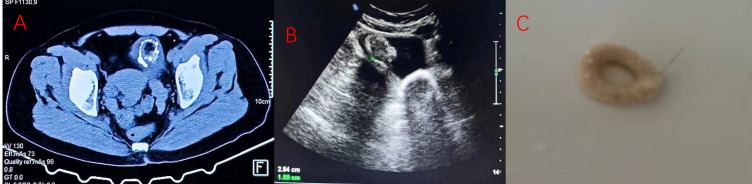

畸胎瘤是一种起源于生殖细胞的肿瘤,通常包含来自所有三个生殖细胞层的可识别组织。畸胎瘤的出现是由于器官受到肿瘤的影响,通常发生在卵巢。畸胎瘤偶尔也见于一些角外器官。然而,原发性畸胎瘤在膀胱是一个罕见的实体。我们在此报告一例膀胱畸胎瘤。一名53岁女性,主诉为尿路中断、腹痛、尿中有结石,经膀胱镜检查诊断,肿瘤切除后接受康复治疗。随后她无症状,进一步的随访观察正在进行中。我们也包括一篇关于原发性膀胱畸胎瘤的文献综述。

Teratoma is neoplasia originating from a germ cell, which usually contains identifiable tissue derived from all three germ cell layers. The presence of teratoma is due to an organ being affected by a tumor, which generally occurs in ovary. Teratoma is also seen occasionally in some extragonadal organs. However, a primary teratoma in the bladder is a rare entity. We hereby present a case of bladder teratoma. A 53-year-old woman whose chief complaints were urinary interruption, pilimiction, and a stone in her urine was diagnosed by cystoscopy and received rehabilitation after tumor resection surgery. She was then symptom-free and further follow-up observation was in progress. We also include a literature review concerning primary bladder teratoma.